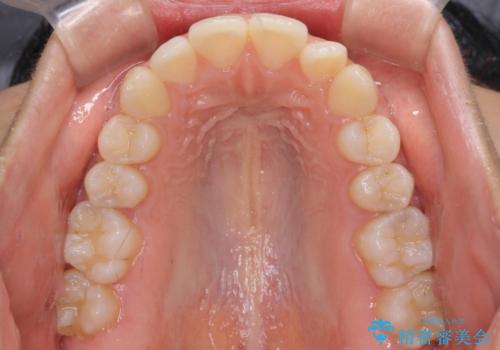

- 出っ歯で唇が閉じにくいとのことで来院された患者様です。

顎先に力を入れないと唇が閉じきれない口元であったので、上下左右の第一小臼歯4本を抜歯して、ワイヤー装置にて矯正治療を行うこととしました。

2年から2年半の治療期間を想定しており、予定通りの期間で無事に終了することができました。

唇や顎先に力を入れないなくてもスムーズに唇を閉じることができるようになりました。